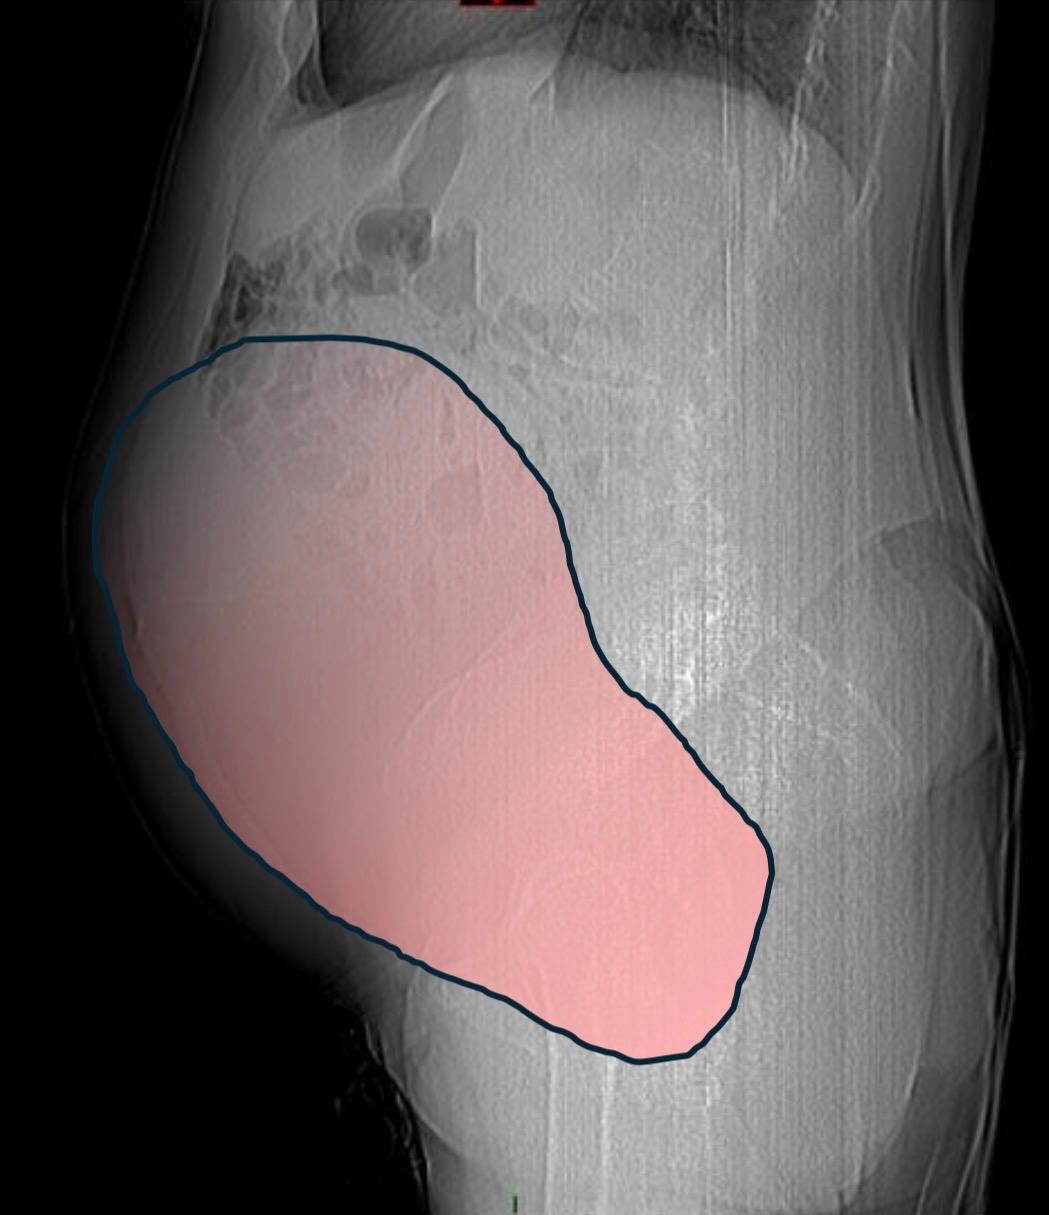

Per mesi la gigantesca cisti ovarica, con un diametro di circa 28 centimetri, è rimasta nascosta, senza dare segnali evidenti. La paziente non si era accorta di nulla. L’allarme è scattato quando la massa, associata alla presenza di una seconda neoplasia intestinale, ha iniziato a comprimere il colon, provocando sintomi acuti e improvvisi, fino a una grave difficoltà intestinale non più ignorabile.

Le dimensioni della cisti

Durante l’intervento emerge tutta la gravità della situazione. La gigantesca neoplasia ovarica viene asportata: pesa circa 6 chilogrammi, con un volume paragonabile a quello di una gravidanza gemellare a termine. Ma non è l’unica minaccia. I sintomi più pericolosi sono legati alla sofferenza intestinale, che richiede un intervento immediato e coordinato di più specialisti.